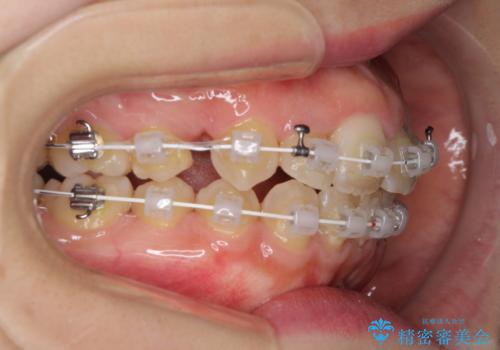

- 矯正装置

- 審美装置

- 右上の八重歯と、左下八重歯を抜いてしまったことを気にして来院された患者様です。

下顎は既に犬歯を1本抜歯しているため、上顎右側第一小臼歯を抜歯し、ワイヤー装置にて歯列を整えることとしました。